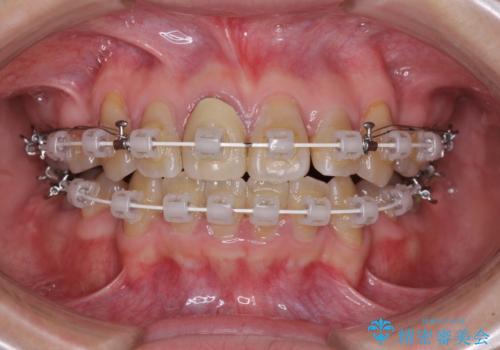

- 審美装置

上下の正中がずれていましたが、抜歯矯正であったので、極力正中位置を合わせるように治療を進めて行きました。

顎間ゴムの使用などにより、正中位置を改善することができました。